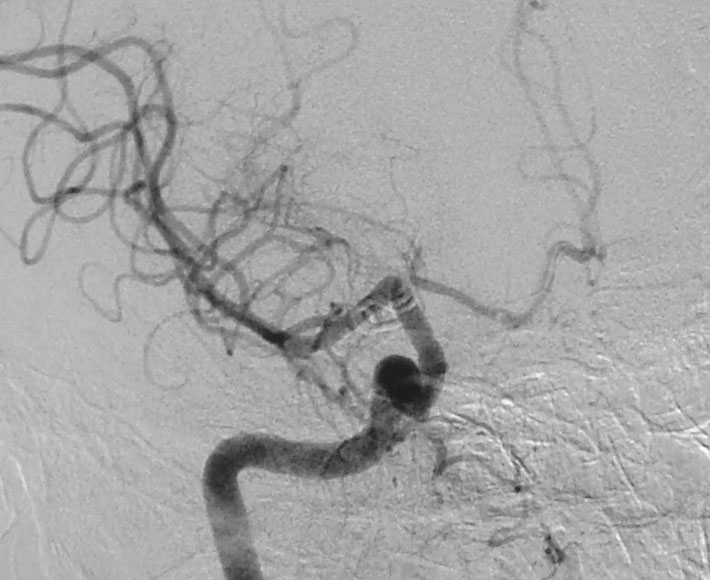

A 38-year-old-male was admitted with sudden onset of severe global headache and vomiting, followed by altereation in sensorium. CT brain showed subarachnoid and intraventricular hemorrhage (Fig 1). MRI brain revealed deep seated right sided thalamic hematoma due to ruptured internal carotid artery bifurcation aneurysm (Fig 2), confirmed by cerebral digital subtraction angiography (Fig 3). He underwent clipping of the aneurysm by transciliary supraorbital keyhole minicraniotomy (see video). Postoperative angiography showed complete occlusion of the aneurysm (Fig 4). When discharged ten days later, there was no neurological deficit (Fig 5).

Fig 3

(Fig 3)

Fig 4

(Fig 4)